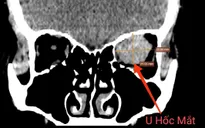

Bệnh nhân T.T.H., (61 tuổi, trú tại Đông Hưng, Thái Bình) đến khám trong tình trạng khối u góc hàm - cổ trái rất to, đau tức, khó chịu, khó thở.

Thời điểm nhập viện tại Trung tâm Ung bướu, kích thước khối u rất lớn, làm biến dạng khuôn mặt, kéo lệch bên mặt trái và bên cổ trái, bệnh nhân có biểu hiện khó thở do khối u chèn ép, đau tức khó chịu vùng mặt trái và cổ trái.

Qua thăm khám và làm các xét nghiệm cận lâm sàng, các bác sĩ chẩn đoán bệnh nhân bị u xơ mạch lành tính. Bệnh nhân được chỉ định phẫu thuật loại bỏ khối khối u và tạo hình lại vùng cổ và vùng mặt.